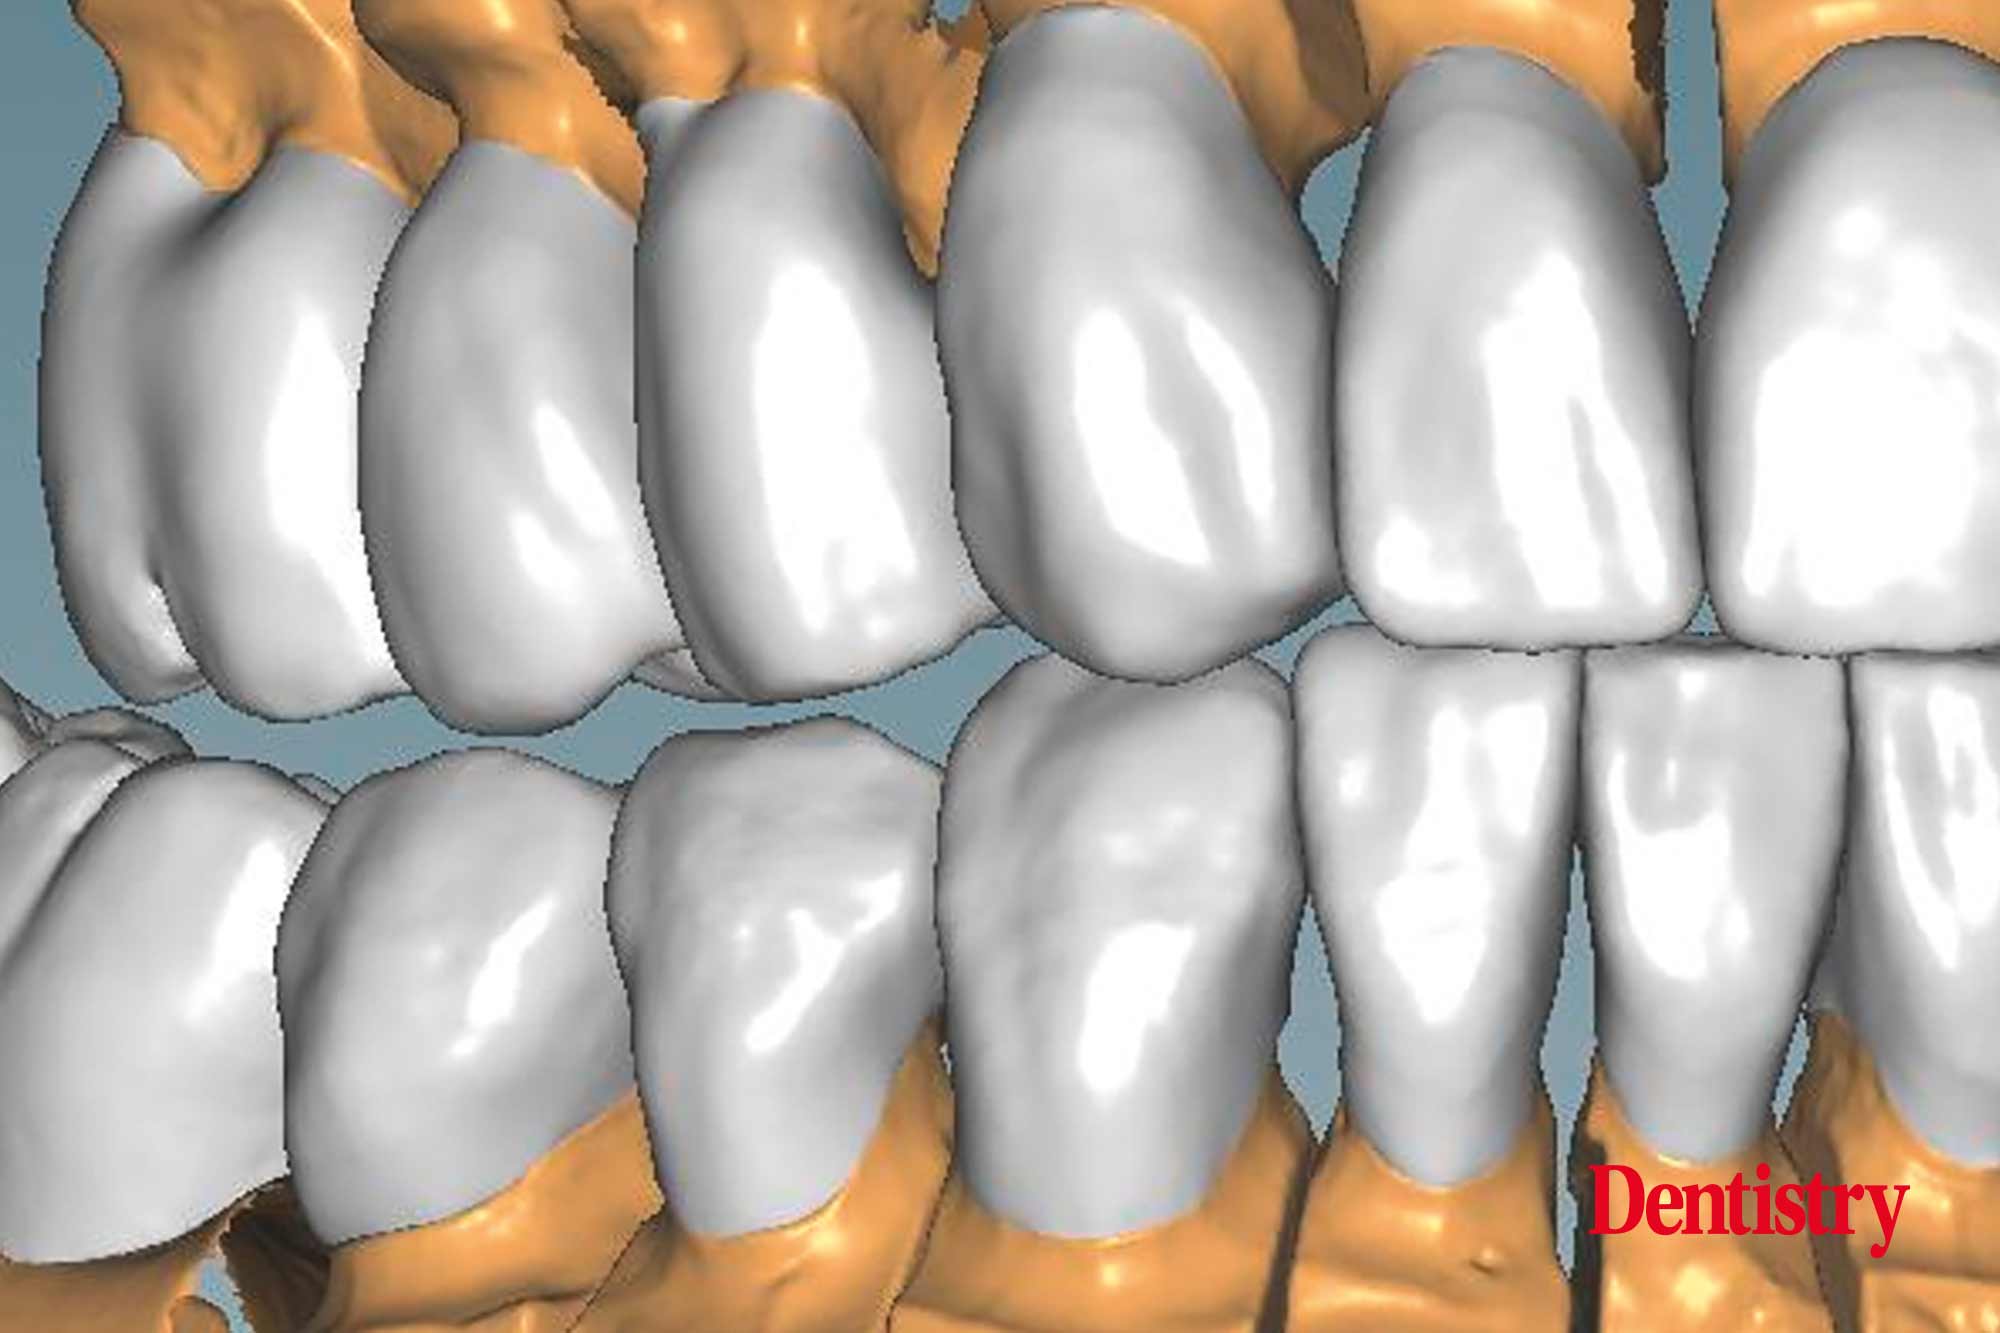

CAD design of the final crowns

Using the CAD software (Figure 12), we were able to round off and refine the areas on the temporary crowns that had been ground and modified intraorally. As a result, this left the remaining areas unchanged.

Figure 13 shows the areas that were adjusted intraorally in green and the remaining unchanged areas in blue. The plan was to fabricate Ceramill Zolid FX crowns on the maxillary teeth first. This is so subsequent corrections on the lower temporary crowns would mean that less corrections would be necessary for the final lower crowns.

Canine guidance with a light group function was created on the Ceramill Mind Wizard.